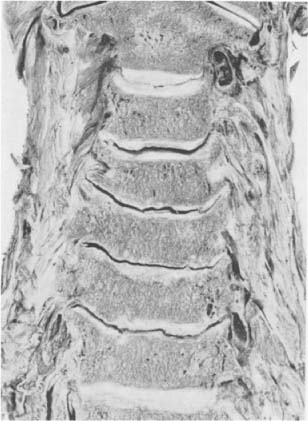

Halswirbelsäule einer 79jährigen Frau. Die seitlich ausgebogenen Processus uncinati führen zu einer starken Verbreiterung vornehmlich der unteren Wirbelkörper. Die in flachem Bogen durchziehenden Zwischen-wirbelspalträume verleihen der Wirbelsäule ein einer chinesischen Pagode ähnliches Aussehen